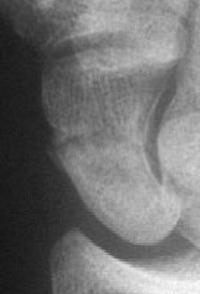

The poorly placed screw remained a source of pain, and the hardware was removed along with a styloidectomy.

Click for larger image

Case 3. Another postop, better screw positioning.